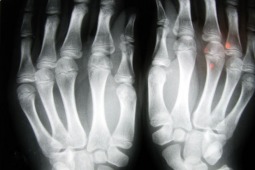

Wynika tak z ich najnowszych badań. „The Times of Israel”, poinformował o odkryciu naukowców z Tel Avivu. Dowodzą oni, że szczury ze złamaniami kończyn szybciej dochodziły do zdrowia, jeśli podawano im kannabidiol (CBD), organiczny związek chemiczny występujący w konopiach.

Zauważono, iż kości zwierząt wyleczonych przy zastosowaniu takiej terapii były znacznie mocniejsze i odporniejsze na urazy. Zdaniem badaczy oznacza to, że przyjmowanie marihuany zmniejsza ryzyko ponownego złamania.